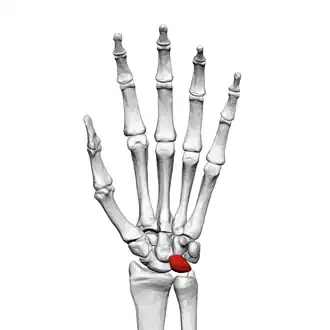

![]() Left hand anterior view (palmar view). Lunate bone shown in red. | |

Lunate bone of the left hand (shown in red). Animation. -